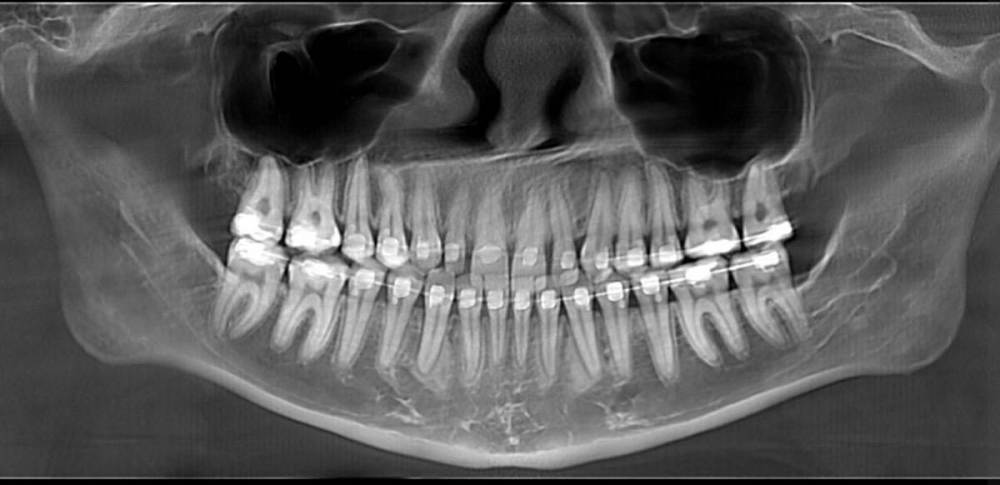

НадеждаВ Опубликовано 3 августа, 2022 Поделиться Опубликовано 3 августа, 2022 (изменено) Добрый день. Имеются 2 шипообразных резца. В стоматологии, где прохожу ортодонтическое лечение убеждают, что просто нарастить только их винирами не выйдет, т.к очень большие расстояния и если закрыть их, то боковые резцы по ширине будут неестественно широкими по отношению к центральным. Уменьшить промежутки тоже не видят возможности, т.к. сейчас передние зубы находятся между двумя нижними, при движении будут друг над другом. Поэтому предлагают установить 6 виниров от клыка до клыка, чтобы закрыть все промежутки и соблюсти соотношение ширины зубов. Действительно ли в моем случае это необходимо и нет реальной возможности ограничиться только двумя реставрациями с сохранением эстетики? Страшно пилить здоровые достаточно эстетичные зубы, особенно центральные резцы. На фото так же макет пластиковый, как мне предлагают сделать. Действительно ли боковые резцы должны быть несколько наклонены к центральным, а не быть абсолютно прямыми и зениты могут быть не четко по центру от зуба, а несколько в сторону уходить? 2. Вопрос касаемо самих виниров. Я хотела бы отбелить свои зубы на сколько получится и чтобы виниры были неотличимы от родных зубов. Я читала, что емах выглядят серовато, подходит ли в моем случае этот способ или лучше виниры, которые делают на рефракторе? Они, как я поняла, выглядят естественнее и тоньше, поэтому и обточки требуют меньше. ( один из Резцов на столько мал, что на него вроде только коронку можно установить). 3. Как оценить опытность врача? У ортопеда опыт всего 4 года, вдруг спилит слишком много. Так же смущает их техник, т.к у него скорее всего тоже небольшой опыт, сможет ли он сделать действительно эстетичную реставрацию? Когда делали макет и меня спрашивали про форму, я сказала, чтобы она максимально была похожа на мою и на макете боковые резцы сделали скошенные, как мои сейчас, но стёсанные, ведь это не эстетично и техник должен был это понимать. Изменено 3 августа, 2022 пользователем НадеждаВ Ссылка на комментарий

НадеждаВ Опубликовано 4 августа, 2022 Автор Поделиться Опубликовано 4 августа, 2022 @chervoncevdaniil спасибо. Да, макет на 6 зубов. Согласна, что выглядит органично, но я переживаю за зубы, ведь они здоровые, нормальные, а если раз их спилить, то все (это не касается боковых Резцов) я переживаю за целесообразность портить эмаль только ради двух миллиметров винира. По поводу макета на два зуба наверно хорошая идея, только когда мне ставили обратно брекеты, то положение зубов немного поменялось, щель между центральными зубами ушла почти ( хотя изначально у меня вообще ее не было), я правильно понимаю, что по идее, если хоть что-то сдвинулось, то по идее нужно вообще опять гипсовую модель переделывать? ещё сканировали челюсть на 3д, но почему-то этот снимок вообще не использовали. Ссылка на комментарий